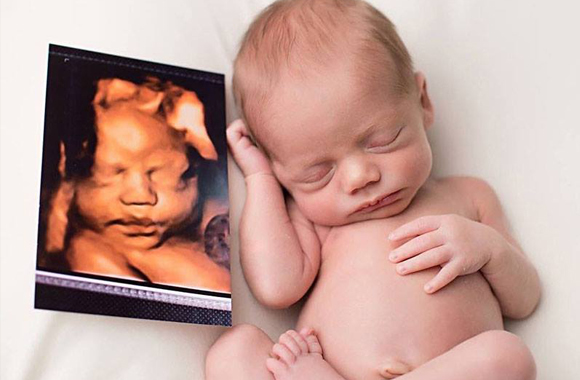

Son las ecografías más realistas que hasta el momento se pueden obtener, ya que, como hemos mencionado, son más nítidas y ofrecen una mejor resolución. Eso da lugar a que tanto la cara del niño como el cuerpo se perciban mucho mejor.

• Este tipo de ecografías están compuestas por imágenes tridimensionales en movimiento de alta resolución que posibilita la visualización de los órganos internos del feto. Gracias al software de tratamiento de imagen, la ecografía se fundamenta en el realismo dando lugar a lo que se ha llamado “ecografía emocional”.